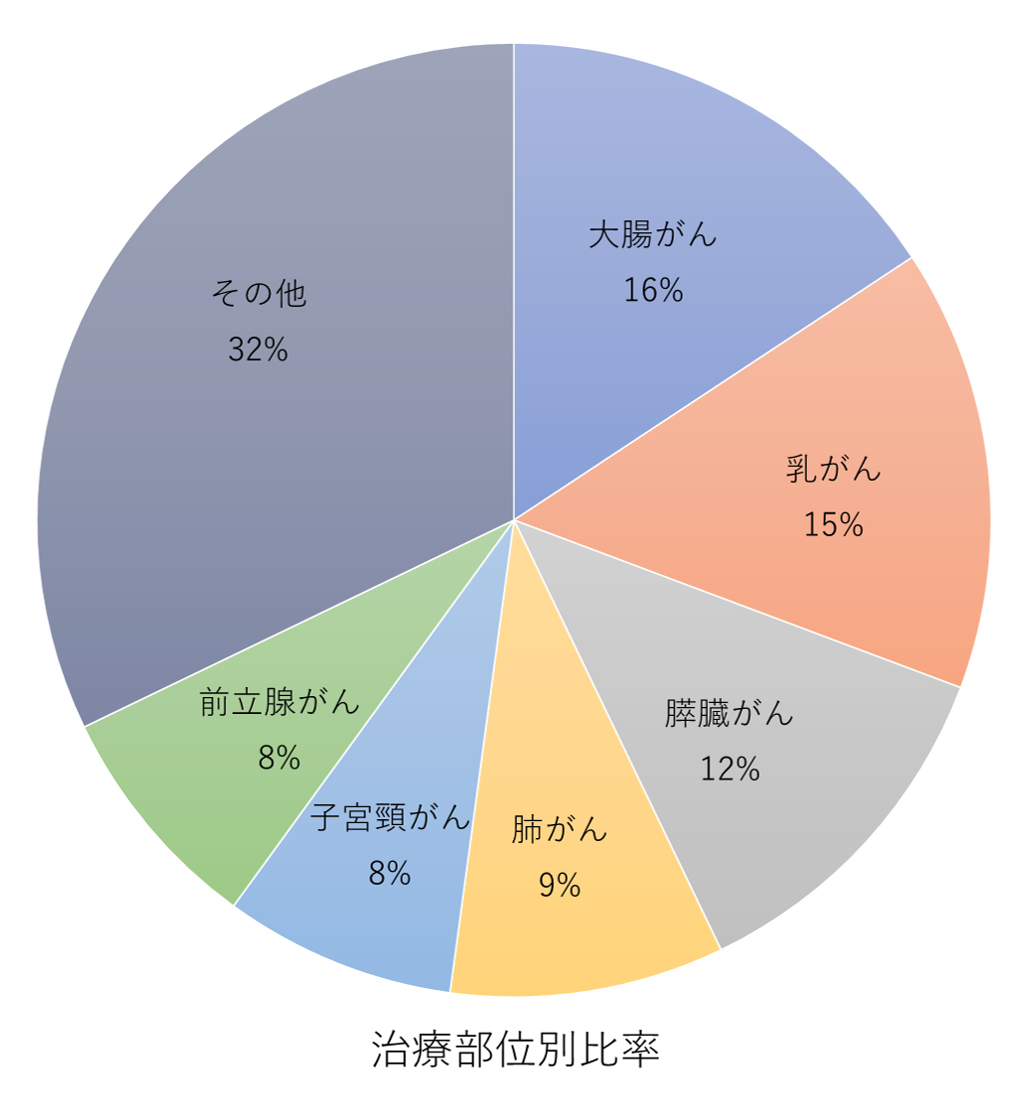

光免疫療法は、治療の中でも特に「その他」と分類されるものが最も多く、全体の32%を占めています。

これは光免疫療法が多様ながん種に対応できることを示しています。次に多く治療されるがん種は「大腸がん」で16%、「乳がん」が15%、「膵臓がん」が12%と続きます。